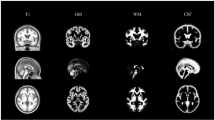

Compared with controls, MWoAs had decreased FA at the vermis VI extending to the bilateral lobule V and the bilateral lobule VI of the cerebellum (Table 2, Fig. 1). Cerebellar tract analysis revealed that MWoAs had higher AD, MD and RD in the right inferior cerebellum peduncle (ICP) (Table 3, Fig. 2). MWoAs had higher AD, MD, and RD in the region of the SpV (Table 2, Fig. 3).